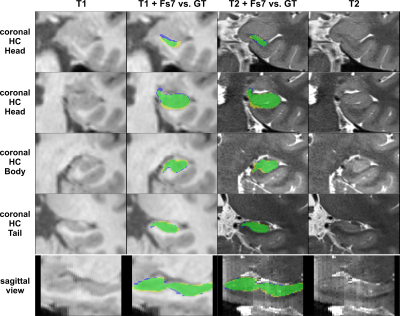

The performance of all segmentation approaches was compared via Dice similarity coefficients (DSC) against our manual GT, averaged over all cross-validation sets. HC segmentation from FreeSurfer v7.3.2 (Figure 4) achieved the lowest results, where using only T1 inputs yields 76.7±4.6% and using T1&T2 inputs results in 77.4±4.3%.

Figure 4: FreeSurfer segmentation. Columns left to right: 1. shows T1 patch; 2. shows comparison of the T1-based FS7-mask vs. the GT; 3. shows the T1+T2 based FS7-mask vs. the GT; 4. shows the registered T2 patch. Top four rows depict coronal slices of the HC-head, HC-body, and HC-tail. The last row shows a sagittal slice with the mask comparison. Legend: green = True Positives, yellow = False Positives, blue = False Negatives; FS7-mask/CNN-mask = yellow+green, manual GT = green+blue.